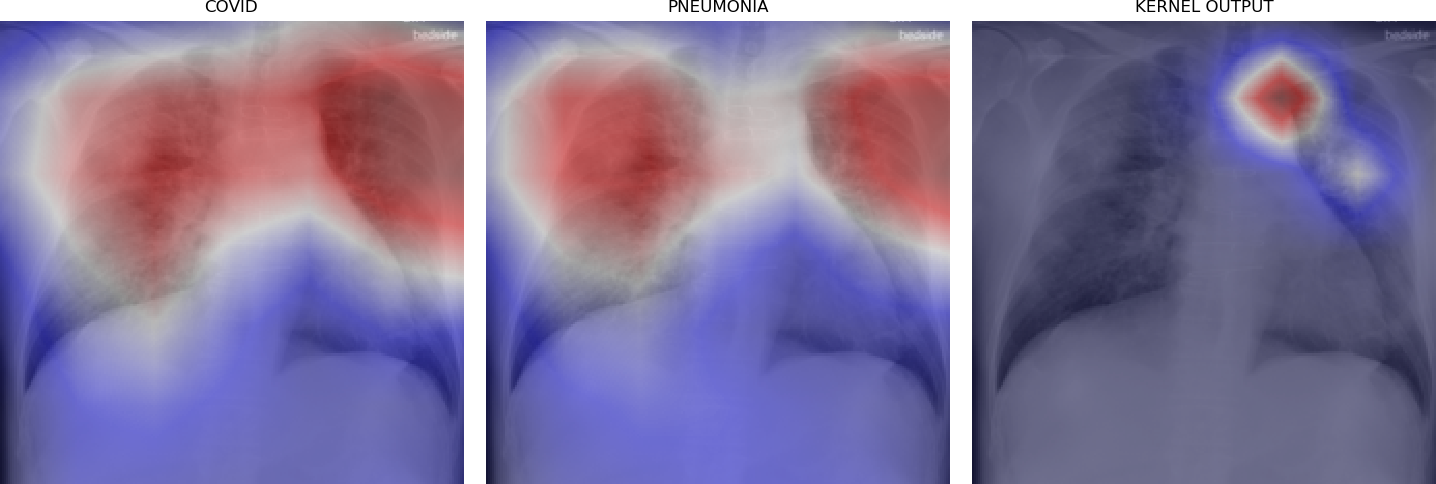

Figure 5 shows triples of X-ray images with superimposed class activation maps for predictions obtained from expert binary models (images one and two) with the third image showing the heat maps computed using our kernel. The intended use of our method is to examine positive classifications from two possibly overlapping classes (i.e. COVID-19, Pneumonia) and extract discriminative features pertaining to the class of interest, i.e. COVID-19. Triples (a)-(f) show positive classifications of COVID-19 and Pneumonia by their respective binary expert models along with class activation maps that localize the image region responsible for that classification. The third image in each triple shows a better localized image region for COVID-19 as computed using our method. Our method is intended to improve explainability of predictions under circumstances where both models return positive classifications resulting in significant overlap in activation maps.

Figure 6 demonstrates the role of the kernel parameter . It controls amplification of the directed differences among the activation maps. Higher values of concentrate the resulting heat map to a smaller region.